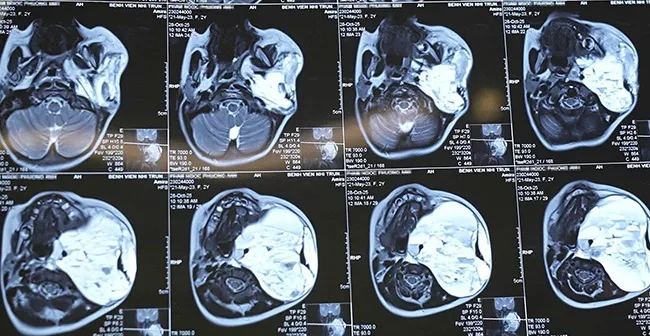

Hình ảnh khối u của bé P.A. Ảnh: BV Nhi Trung ương

Khi được chuyển đến Bệnh viện Nhi Trung ương, tình trạng của bé P.A. diễn biến rất xấu. Trẻ suy hô hấp nặng, phải đặt nội khí quản và thở máy hỗ trợ. Kết quả chụp cộng hưởng từ (MRI) cho thấy khối u kích thước “khổng lồ” (86x101x99mm), chiếm tới 3/4 vùng cổ, đang chảy máu cấp tính bên trong. Khối u chèn ép, đẩy lệch hoàn toàn thanh quản, khí quản và thực quản, gây hẹp lòng thanh hầu, đe dọa trực tiếp tính mạng trẻ do nguy cơ suy hô hấp, suy tuần hoàn và mất máu cấp.